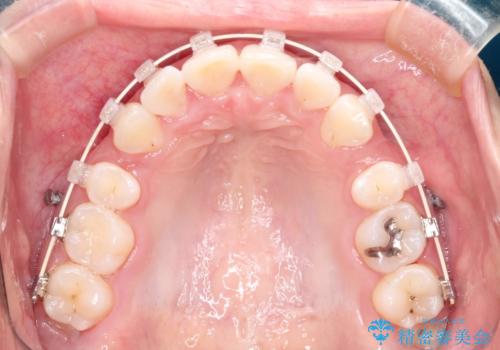

- 矯正装置

- 審美装置

- 治療期間

- 2年6ヶ月